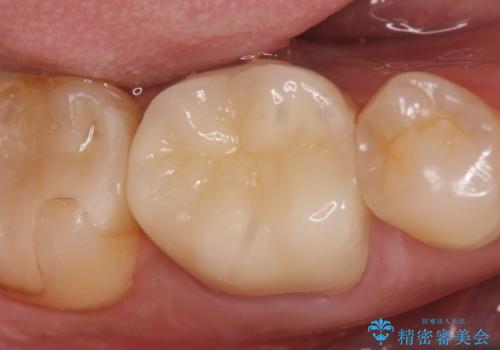

症状が治まったのを確認後、オールセラミッククラウンによる補綴を行いました。

今回用いたオールセラミッククラウンはジルコニアフレームという白い素材の上にセラミックを盛っているため、審美性が非常に高いのが特徴です。

また、ジルコニアは人工ダイヤモンドの材料にも使われているほど高い強度を持っており、そのためオールセラミッククラウンは審美性だけでなく、奥歯やブリッジの補綴も可能とするクラウンです。